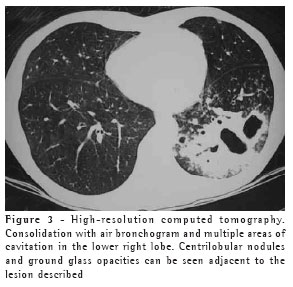

The most frequent finding in the imaging, present in the seven patients, was ill-defined consolidation (Figures 1, 2, 3 and 4). Five of patients presented air bronchogram, principally at the periphery of the lesion. In three cases, the consolidation was organized in the form of a mass. In six of the seven patients, irregular areas of cavitation were observed within the consolidations. Multiple cavitations were seen in five patients, and a singular cavitation was observed in one patient. In the patient presenting no cavitation, there were hypodense areas suggestive of necrosis (Figure 5). Only one of the patients presented air-fluid levels within the cavities.

Cavitated lesions predominated in the upper lobes, four in the right lobe and one in the left lobe. In one patient, the middle lobe was also affected. In two cases, such lesions occurred in the lower lobes, one in the right lobe and one in the left lobe. In four cases, the lesions affected only the lobes mentioned above and were therefore unilateral. In the remaining three cases, the contralateral lung was also affected, albeit to a lesser degree. In one case, there was also relatively thin-walled, multiloculated cavitation, without an air-fluid level, in the middle lobe.

In our study, the principal pattern of pulmonary involvement was air bronchogram and cavitation, which was present in six patients. There were multiple cavitations in five cases and a singular cavitation in one. The consolidations were large and had irregular contours. The air bronchograms were located in the peripheral portions of the lesions. The pulmonary lobe most frequently involved was the upper right lobe, which was affected in four patients. Most of the case review studies confirm these findings.(2,5) Some studies have reported that, although cavitation might not be present at the time of diagnosis, it develops over the course of the disease.(4) In the sample evaluated in the present study, air-fluid levels within the cavitations were seen in only one patient.